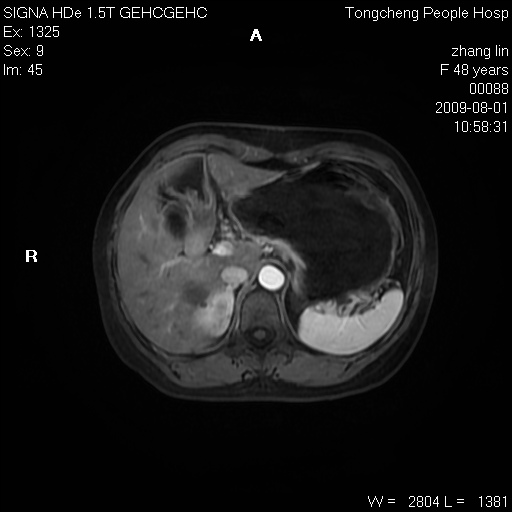

女,48岁。健康体检,彩超发现右肾占位性病变。平素健康。

临床诊断:右肾占位性病变,性质待定(囊肿?肿瘤?)。

上中腹部mr平扫+增强扫描,图像如下:

右肾上极见一类圆形病灶,t1wi呈等信号t2wi呈等高混杂信号,三期增强无强化,边界清---考虑囊肿出血。

同反相位均表现为等信号,病变无强化,考虑含蛋白的囊肿可能,弥散加权相或许有些帮助,

肝囊肿